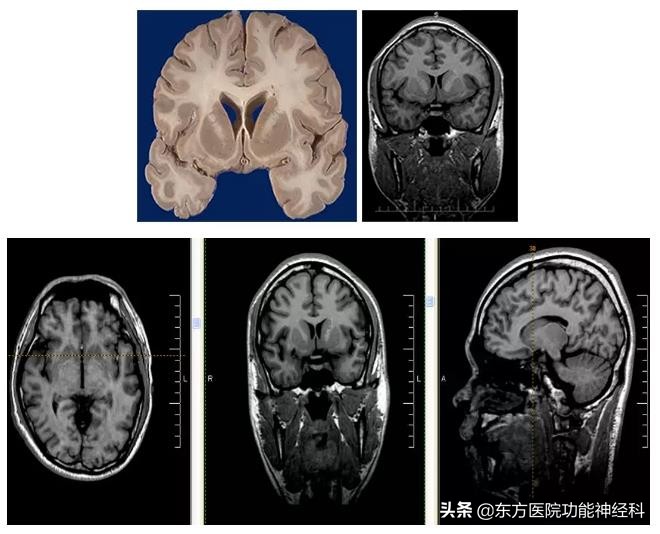

一个50年代脑白质切除术病人颅脑CT MR表现

计算机辅助立体定向手术规划及手术导航技术具有手术创伤小、定位精度高等优点,在国外已经逐步成为神经外科手术的常规治疗手段之一。目前,立体定向设备在我国部分医院的神经外科已经投入使用,其中计算机手术计划系统占据了重要的地位。 Target软件是核心软件,可以将患者的各种资料进行图像融合,使病人解剖、病理、生理等多方面的数据进行整合。本系统应用的是CT/MR图像融合技术。CT图像利用X线扫描技术成像,可以清晰的显示大脑的骨性标志,图像稳定,具有很高的空间分辨率,但对大脑组织分辨率差,很难区分大脑灰白质和脑内常用神经核团,特别是对于后颅窝结构显示不清;MR图像具有极高的组织分辨率,可以清晰显示灰白质结构,对基底节、丘脑、黑质、红核、杏仁核、内囊前肢、尾核下束等结构有清晰的显示。但是由于MR是磁源性成像,磁场容易受到地磁等多种因素的干扰,同时,磁力线通过定位框架、头皮和颅骨不同的界面时,磁力线发生偏转,从而使图像发生漂移,特别是外周的脑组织。

另外,尽管目前定位框架采用的合金对磁场影响很小,但其作用仍不可低估。而我们应用图像融合技术,病人不装头架行常规MR扫描,带头架后行CT扫描,然后在计划系统内应用互感技术进行图像融合,充分利用了CT图像的高空间分辨率和MR图像的高组织分辨率,大大减少了MR图像的漂移,从而使定位的准确性大大提高。在手术计划系统中,我们将患者的MR资料进行标准化或格子化处理,再和标准的脑立体定向图谱进行融合,从而使丘脑各亚核的直视定位成为可能。